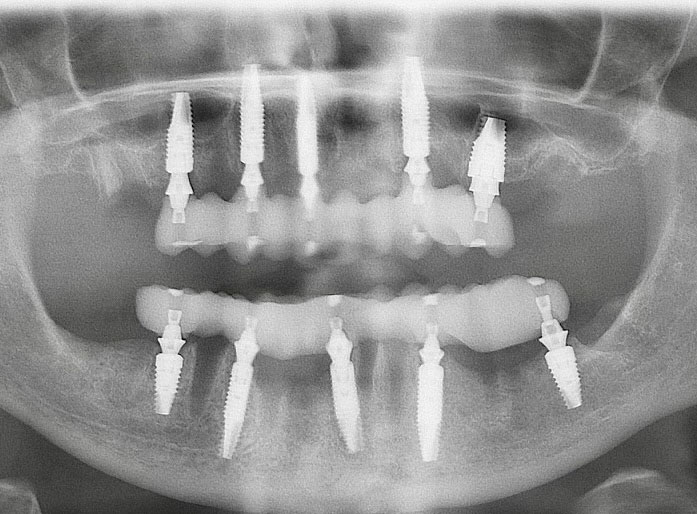

Fig 6. Postoperative panoramic radiograph on the day of surgery.

Figure 6